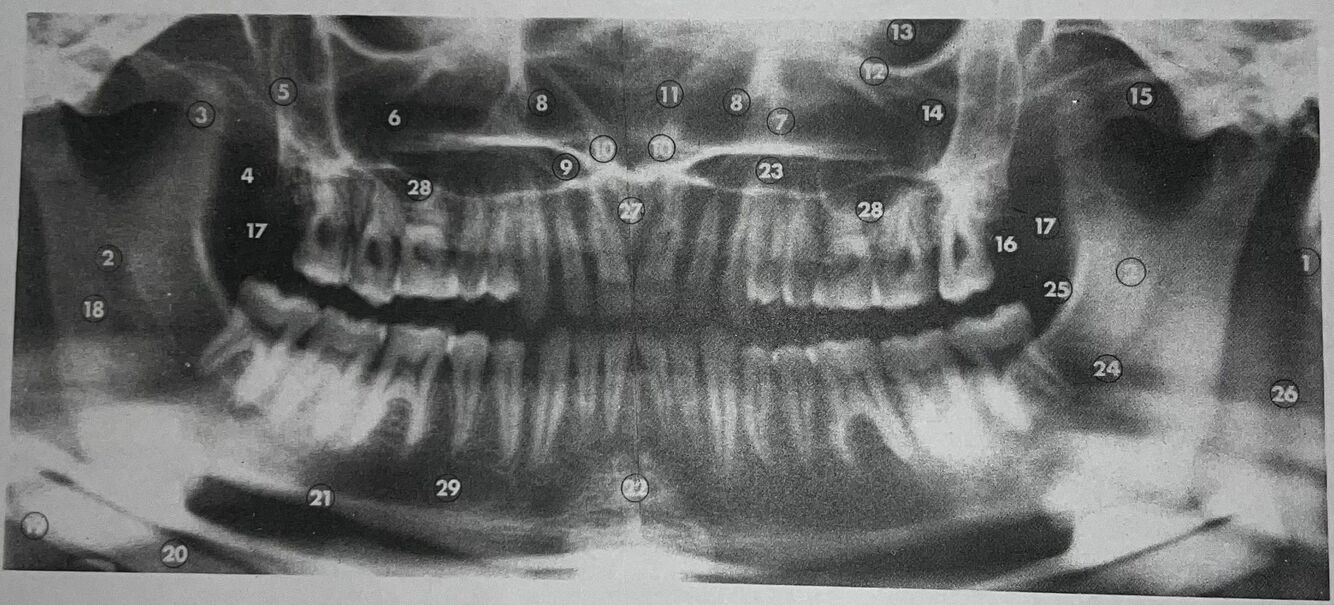

what is 1

mastoid process

what is 2

lingula

what is 3

coronoid process

what is 4

lateral pterygoid plate

what is 5

posterior wall of antrum

what is 6

antrum (maxillary sinus)

what is 7

anteromedial wall of antrum

what is 8

inferior concha

what is 9

floor of nasal fossa

what is 10

anterior nasal spine

what is 11

nasal septum

what is 12

infraorbital ridge

what is 13

orbital cavity

what is 14

malar process

what is 15

zygomatic arch

what is 16

maxillary tuberosity

22

mental protuberance

what is 23

mandibular canal

what is 25

internal oblique line

what is 26

superimposition of right jaw

what is 27

incisive canals

what is 28

floor of antrum

what is 29

mental foramen